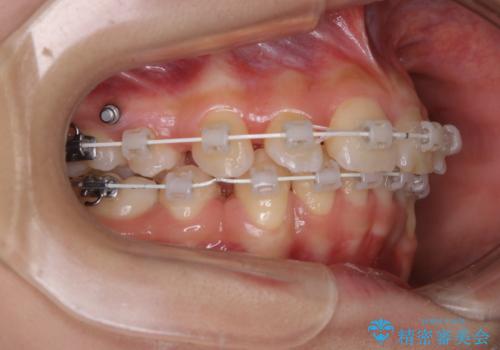

- 矯正装置

- 審美装置(ワイヤー)

- 出っ歯が気になるとご相談にいらした方です。抜歯して歯を並べました。深かった噛み合わせも改善させることが出来ました。

噛み合わせが元々深い方は一般的に噛む力が強く、治療に時間がかかる傾向にあります。治療前の想定よりも短期間でスムーズに治療を終える事ができ、大変喜んでいただけました。リテーナーによる保定もしっかり行っていただいており、後戻りなく快適にすごして頂けているとのことです。